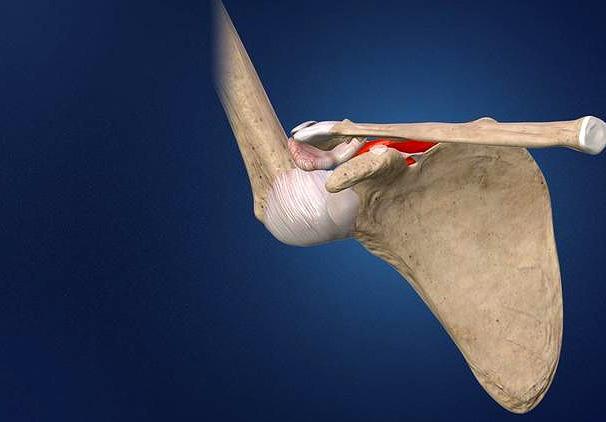

肺上沟癌会导致肩痛

看我们同事母亲ct的时候,谢医生第一眼关注的就是这个位置,肺上沟!因为在这个位置有一种癌症叫做肺上沟癌,是肺癌的一种,会诱发患者出现肩痛,这个癌症的名称并不是由病理分型来确定的,而是由位置决定的,足见它的特殊性!

大家可以把肺上沟这个位置理解为肺部的顶点周边,在这个位置有非常复杂以及重要的结构存在,比如头臂静脉、锁骨下动脉、膈神经、臂丛神经和迷走神经等。

当患者罹患这个位置肿瘤以后,肿瘤如果不是特别的大,这往往不会有任何的症状,甚至都没有肺癌患者常见的咳嗽、呼吸困难、咳痰等表现,症状可以说是非常的隐秘。但是随着肿瘤的生长变得越来越大,肿瘤有可能最终突破肺的表面,侵犯到前面所说的,在肺上沟这个位置非常重要的结构,当侵犯到闭孔神经、胸膜、筋膜、肋骨等结构,就会诱发患者出现尖锐的后背疼,患者的腋窝和肩胛骨的区域也有可能出现剧烈的疼痛,有可能会蔓延到头部、颈部或者是手臂。

如果侵犯到同侧的交感神经节以后啊,患者还会表现出霍纳综合症,比如眼睑下垂,眼球内穴,瞳孔明显的缩小,有一些患者会表现出来同侧额部不能排汗。